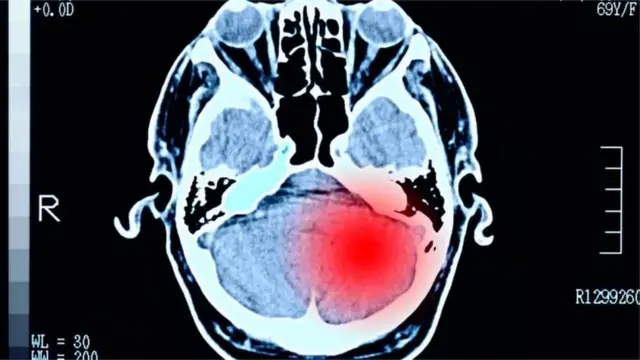

- బెయిన్ ట్యూమర్

బ్రెయిన్ ట్యూమర్, కార్సినోమా ముఖ్యంగా జీర్ణవ్యవస్థలో వచ్చేవి అత్యంత ప్రమాదకరమని ప్రొఫెసర్ స్టార్క్ వివరించారు.

"బ్రెయిన్ ట్యూమర్ వస్తే చాలా కష్టం. దానికి చికిత్స, తరువాత కోలుకునే అవకాశాలు చాలా తక్కువ" అని ఆయన చెప్పారు.

మైకం కమ్మడం, కడుపులో వికారం, జ్ఞాపకశక్తి సమస్యలు, ప్రవర్తనలో మార్పులు, బలహీనత, శరీరంలో కొన్ని భాగాలకు పక్షవాతం, దృష్టి లోపం.. ఇవన్నీ ఈ క్యాన్సర్ లక్షణాలు.